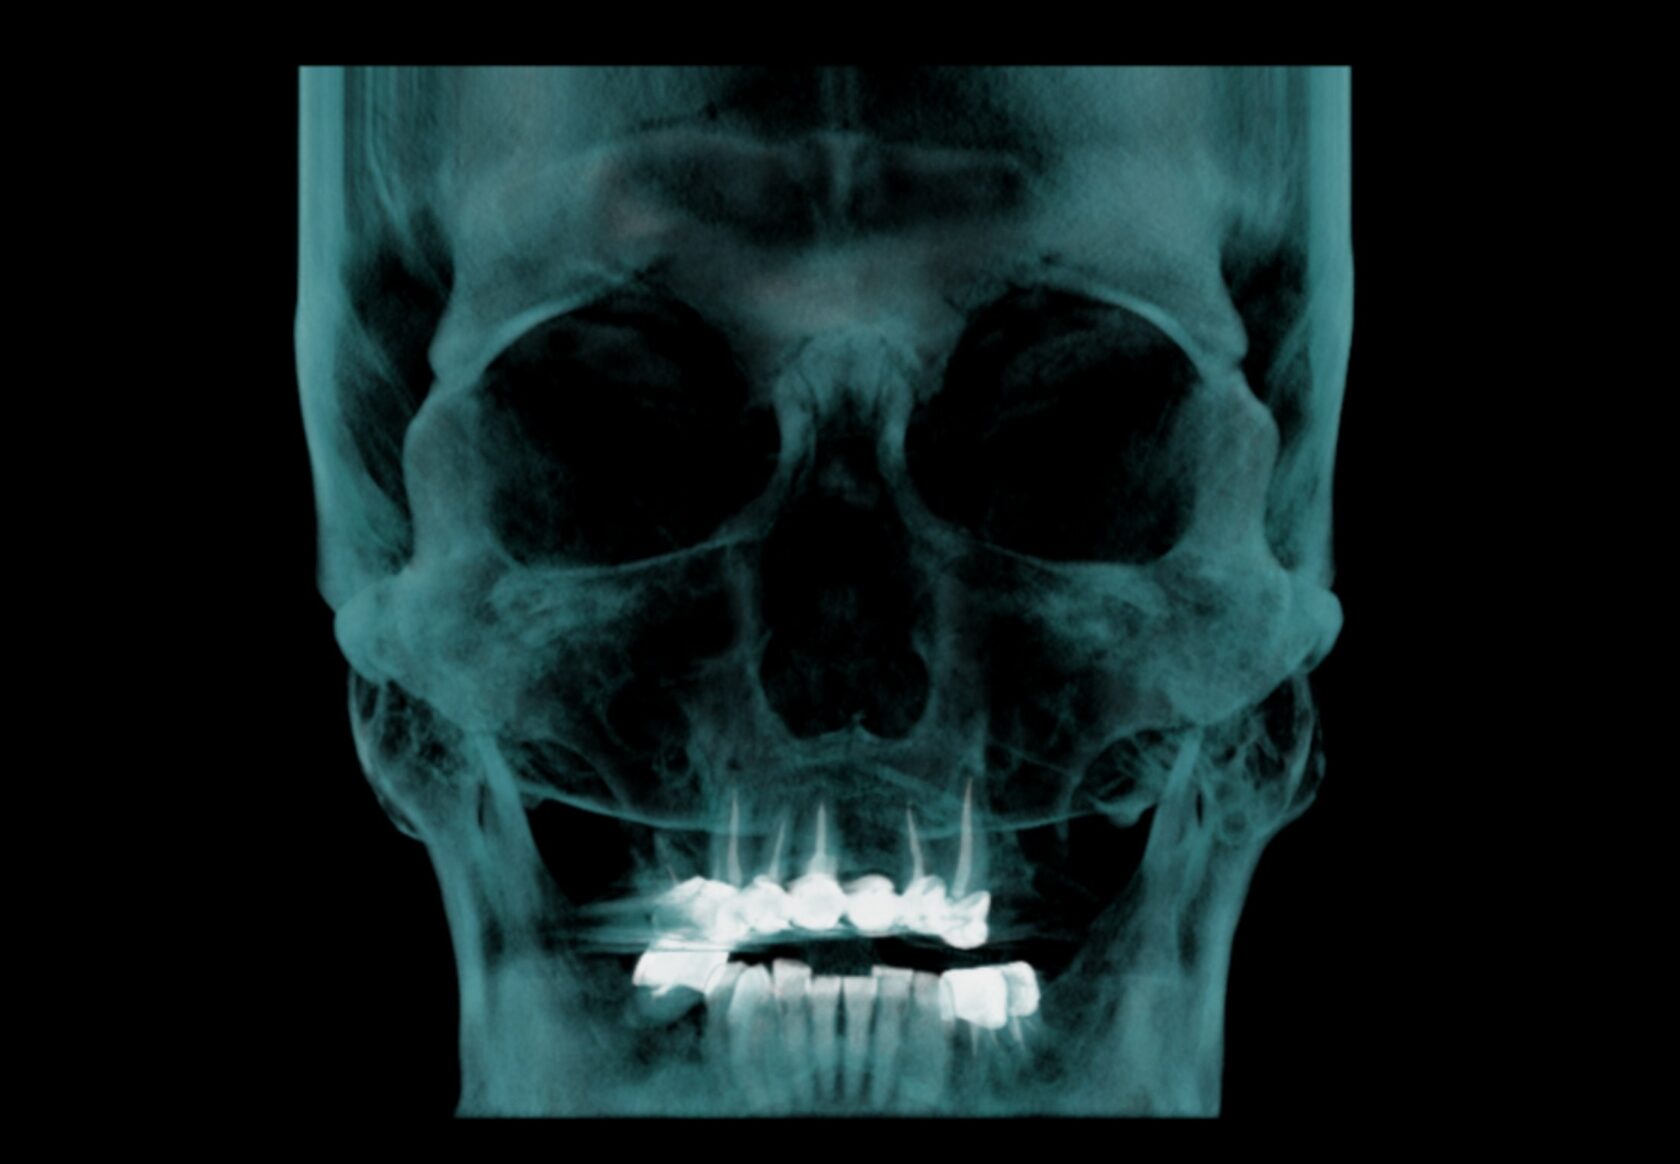

Оценка всего челюстно-лицевого комплекса (лицевого скелета) включая верхнюю и нижнюю челюсти, ВНЧС, дыхательные пути, остиомеатальный комплекс и придаточные пазухи носа, профиль мягких тканей.